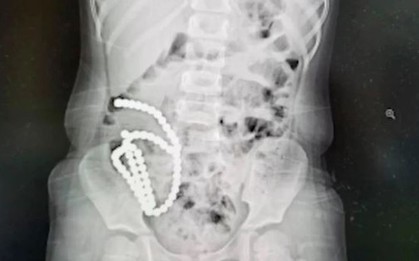

Một người đàn ông 68 tuổi ở Hà Nội may mắn thoát khỏi nguy kịch sau khi nuốt phải thứ quen thuộc dài gần 7cm. Các bác sĩ nhanh chóng gắp ra "sát thủ thầm lặng" rất may không đe dọa tính mạng.